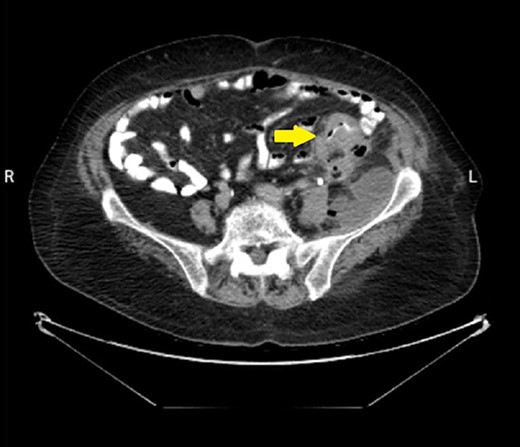

An 82-year-old female patient with a known history of sigmoid colon adenocarcinoma diagnosed 1 month ago (Fig. 1), presented to the Emergency Department due to hip pain for 10 days, associated with abdominal pain, bloody diarrhea, and loss of appetite. The patient has a medical history of hypertension, and congestive heart failure with ejection fraction 20%. Her vitals were a temperature of 38.3°C, heart rate of 102/min, respiratory rate of 22/min, blood pressure of 90/60 mm Hg, and pulse oximetry of 94%. On examination, there was a large, tender erythematous swelling on the proximal anterolateral aspect of the left thigh. The swelling was fluctuant, with a black necrotic center (Fig. 2). Laboratory tests revealed an elevated white blood cell count, C-reactive protein level, and signs of acute kidney injury (Table 1).

Abdominal CT scan with contrast showed the neoplasm and the presence of fluid collection (done at the time of the diagnosis of CC).